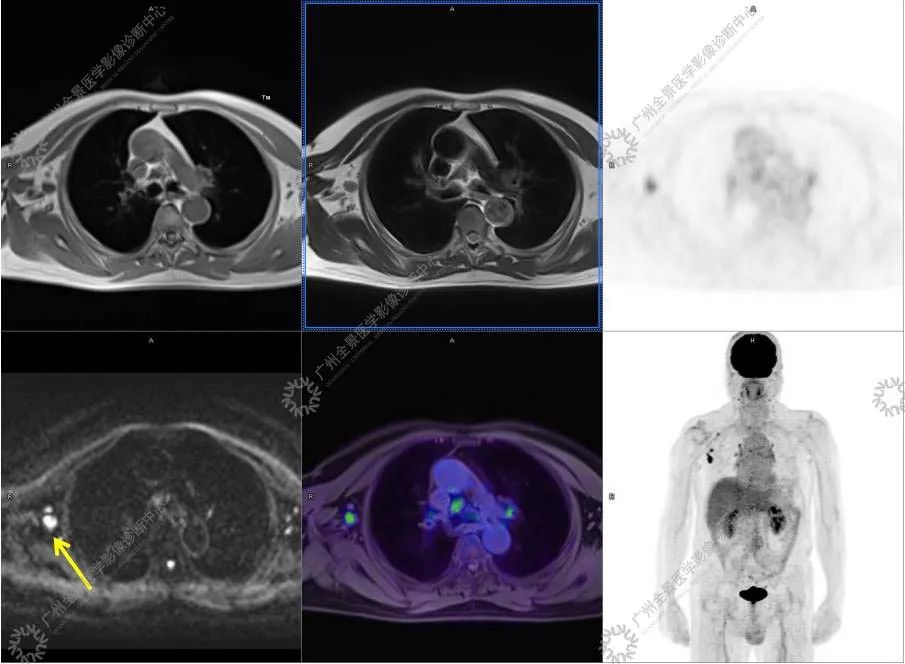

肉眼所见:(胸壁肿物) 灰白色结节一枚:3x2.5x1.7 cm, 切面灰白,质中。

结合影像及实验室检查,临床最终考虑 IgG4 相关性疾病。

●18FDG-PET/CT 作为一种解剖和功能结合新的显像方法,IgG4-RD 的诊断及鉴别诊断中存在着巨大的优势:

●18FDG-PET/CT 扫描作为一种全身检查,有着传统影像学局部扫描无法比拟的优势,PET/CT 扫描不仅可以发现以临床症状为导向的局部病灶,更可以发现远隔部位的受累病灶。